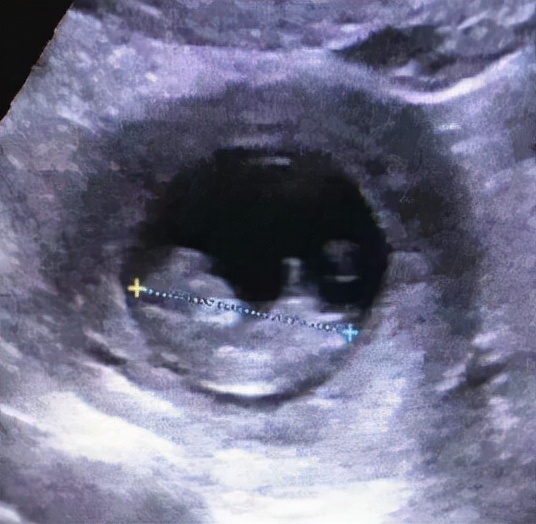

术后病理回示:左侧输卵管妊娠。11.13复查B超:宫腔内扫见49*33*48妊娠囊,其内见卵黄囊及胚芽,有心管搏动,头臀长37mm,提示:早孕。患者无腹痛及阴道流血,11.17再次复查B超无异常后,吴女士终于露出了开心的笑容,与家人愉快的办理了出院。